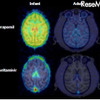

抗不整脈薬のベラパミルでは2.3倍、未成年者の副作用が指摘されている抗インフルエンザ薬のタミフルでは約1.3倍、幼少期のサルでは成熟したサルに比べて速く脳へ取り込まれることがわかったという。